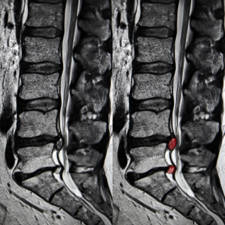

RMN. Mediante la resonancia magnética podremos determinar si hay un resto de hernia discal o si la descompresión ha sido insuficiente, si añadimos contraste a la resonancia se puede diagnosticar la existencia de fibrosis epidural y si esta es lo suficientemente voluminosa como para atrapar a la raíz nerviosa.

Parece que los síntomas del síndrome post-laminectomía podrían estar causados por una aracnoiditis.

La inflamación de la aracnoides produciría fibrosis intradural y agrupamiento de las raíces nerviosas desarrollando los síntomas de los que os hemos hablado.